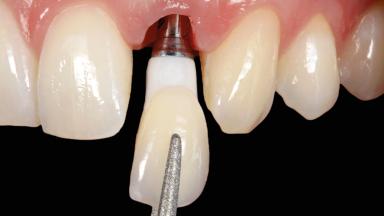

Immediate Implant Placement and Immediate Provisionalization with a Prefabricated-Shell Provisional Crown

In this case, Arndt Happe describes how he achieved a stable outcome at 5 years by giving careful attention to the coronal aspect of the transmucosal area of the provisional, creating a slim emergence profile.

Biological Screw-retained restorations with appropriate contours